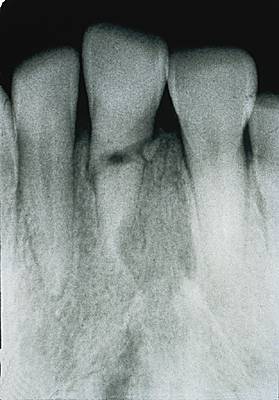

fracture dentaire

Lésion qui peut affecter l'émail et la dentine, ou parfois même la pulpe d'une dent.

D'origine traumatique, parfois favorisées par une carie, les fractures dentaires peuvent être horizontales, verticales ou obliques.

Les fractures horizontales ou obliques sont très fréquentes en milieu scolaire, surtout sur les incisives. La fracture peut être superficielle et ne léser que l'émail ou affecter aussi la dentine, provoquant une sensibilité au froid et au sucre. On reconstruit alors la dent par collage. Lorsque la fracture est profonde et affecte la pulpe, on dévitalise la dent. Cependant, chez un enfant de moins de 12 ans, il est important de maintenir la vitalité de la dent jusqu'à l'édification complète de sa racine.

Les fractures verticales nécessitent l'extraction de la dent.